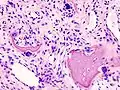

While osteoarthritis is a degenerative joint disease that may cause gross cartilage loss and morphological damage to other joint tissues, more subtle biochemical changes occur in the earliest stages of osteoarthritis progression. The water content of healthy cartilage is finely balanced by compressive force driving water out and hydrostatic and osmotic pressure drawing water in.[36][37] Collagen fibres exert the compressive force, whereas the Gibbs–Donnan effect and cartilage proteoglycans create osmotic pressure which tends to draw water in.[37]

However, during onset of osteoarthritis, the collagen matrix becomes more disorganized and there is a decrease in proteoglycan content within cartilage. The breakdown of collagen fibers results in a net increase in water content.[38][39][40][41][42] This increase occurs because whilst there is an overall loss of proteoglycans (and thus a decreased osmotic pull),[39][43] it is outweighed by a loss of collagen.[37][43]

Other structures within the joint can also be affected.[44] The ligaments within the joint become thickened and fibrotic, and the menisci can become damaged and wear away.[45] Menisci can be completely absent by the time a person undergoes a joint replacement. New bone outgrowths, called "spurs" or osteophytes, can form on the margins of the joints, possibly in an attempt to improve the congruence of the articular cartilage surfaces in the absence of the menisci. The subchondral bone volume increases and becomes less mineralized (hypomineralization).[46] All these changes can cause problems functioning. The pain in an osteoarthritic joint has been related to thickened synovium[47] and to subchondral bone lesions.[48]